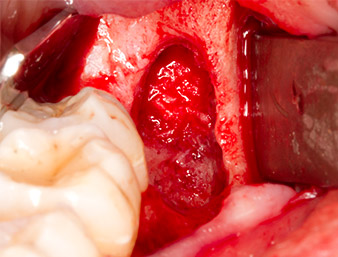

Tessuto di granulazione

Fig. 4: Due retrattori Langenbeck e una curette espongono l'area dell'intervento. È visibile il tessuto di granulazione della prima osteotomia non completamente cicatrizzata.

Il tessuto al di sopra del residuo di radice non era completamente ossificato ed era costituito per la maggior parte da tessuto di granulazione modificato dall'infiammazione (Fig. 4).